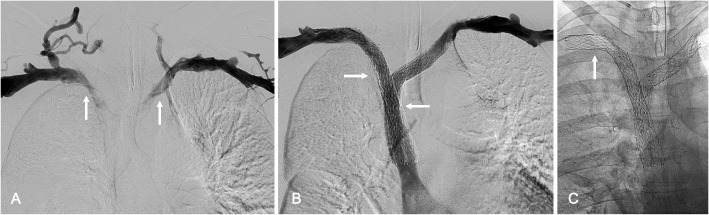

Methods: Thirty-eight patients (43 affected limbs) with symptomatic ASVT and no prior treatment or surgical decompression underwent endovascular placement of dedicated venous stents across the thoracic outlet with Abre Venous Stents (Medtronic, Dublin, Ireland), Venovo Venous Stents (BD, Franklin Lakes, NJ, USA), or Vici Venous Stents (Boston Scientific, Marlborough, MA, USA). Stents were extended peripherally to the subclavian or axillary veins and centrally to the brachiocephalic vein or SVC. Technical success was defined as successful stent deployment across the costoclavicular space, and clinical success as symptomatic improvement.

Results: Stent placement was technically successful in all 43 limbs (100%), with clinical improvement observed in 97.4% of patients. The one patient without clinical improvement experienced early thrombosis of the stent, requiring mechanical thrombectomy and additional stenting. Follow-up CT venography at a mean of 301.3 days demonstrated high primary stent patency rates (81.4%), with stent crushing observed in only 7.0% of limbs and no instances of stent fracture. Adverse events were limited, including two access site hematomas and one hypotensive episode, all of which resolved without evidence of long-term complications.